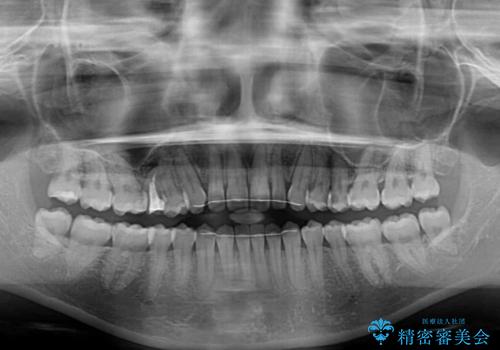

空隙歯列(すきっ歯)は、舌の突出癖をある程度改善できたとしても、後戻りにより隙間が開きやすいと言われています。

裏側から細いワイヤーで保定するとともに、睡眠時のマウスピース装着を徹底していただくことで、後戻りを最小限にとどめます。